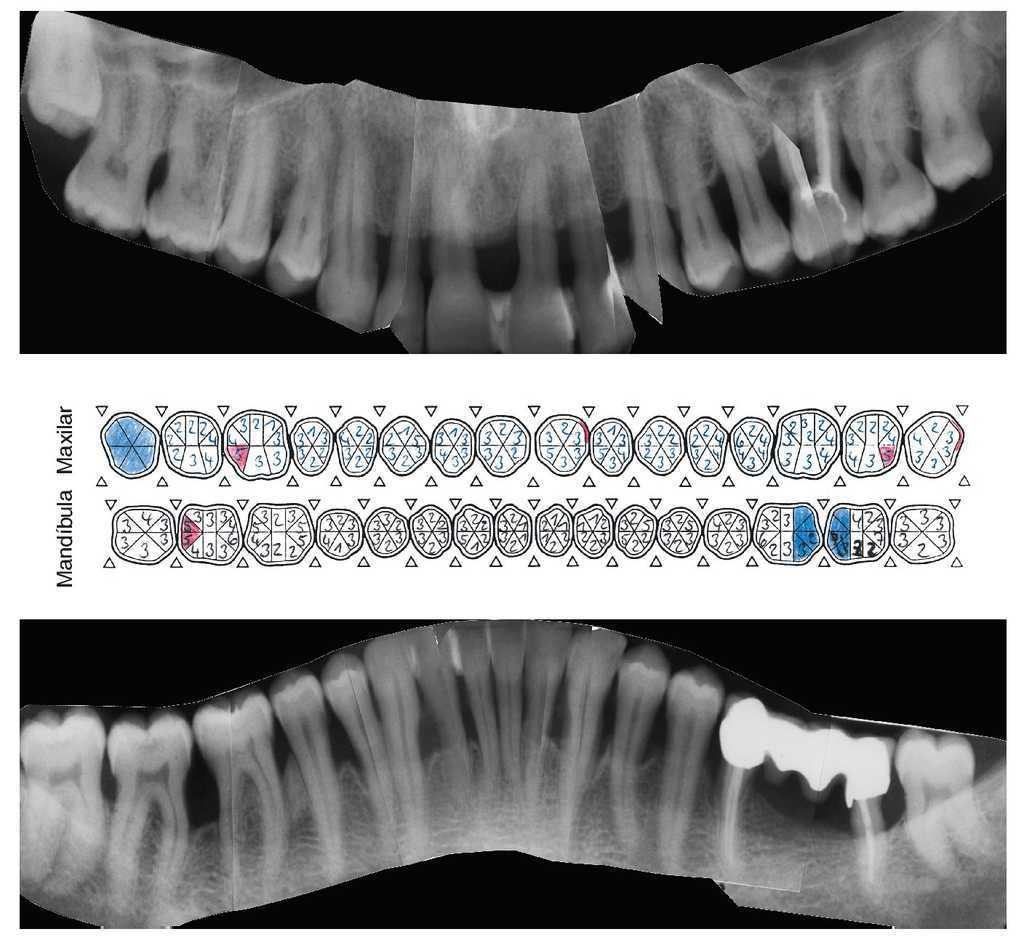

La bibliografía ofrece evidencias de un pronóstico en general muy favorable de los dientes tratados de lesión periodontal. Los datos de una gran cantidad de estudios insisten con vehemencia en la importancia del TPA para la conservación a largo plazo de las estructuras periodontales anteriormente dañadas. El tipo inicial de periodontitis que dio lugar al cuadro clínico no parece desempeñar un papel preponderante en el establecimiento del pronóstico (figs. 1a a 1e).

Figura 1a. Situación periodontal de un paciente de 28 años de edad no fumador en el año 1995.

Figura 1b. Radiografía panorámica en la que el periodoncista ha marcado las piezas dentales con un pronóstico muy desfavorable: 24, 26, 36, 41, 42, 46 y 47.

Figura 1c. Serie de radiografías periapicales tomadas en 1996.

Figura 1d. Situación periodontal del paciente no fumador a los 38 años de edad (año 2005). Reevaluación de las profundidades de sondaje y de la tendencia al sangrado, al principio 3 veces al mes y más tarde de 3 a 4 veces al año, en presencia de una higiene oral excelente.

Figura 1e. La situación periodontal registrada en el año 2006 muestra las profundidades de sondaje residuales y los dientes ausentes, además de la pérdida de inserción y las recesiones aparecidas.